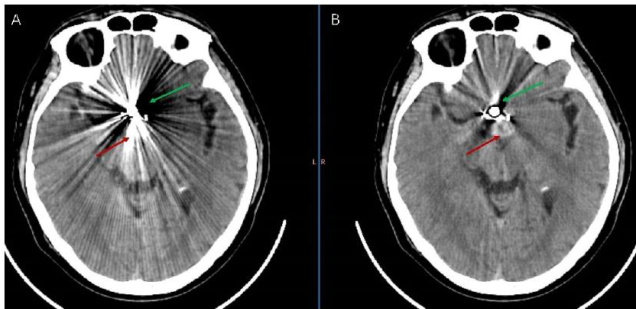

CT成像中金属伪影产生机制及校正方法的研究进展

计算机断层扫描(Computed tomography,CT)以其快速成像和精细的解剖结构显示,已成为现代医学影像学中不可或缺的工具。(剩余17338字)